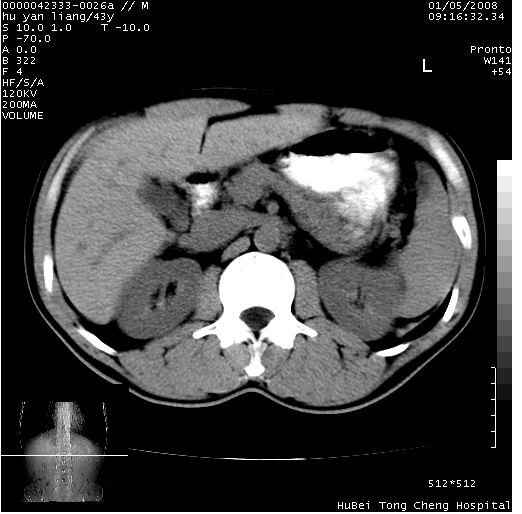

患者 男,43岁。右上腹不适1年余。既往有“肝右叶肝脓肿”病史,经保守治疗后痊愈。

上中腹部ct轴位平扫+增强扫描(层厚10mm,螺距1.0,重建间隔10mm),图像如下:

肝右上叶偏后方较大团片状钙化灶,支持:肝脓肿后遗改变!

肝右叶后段团块状钙化灶,结合病史考虑肝脓肿痊愈后表现。